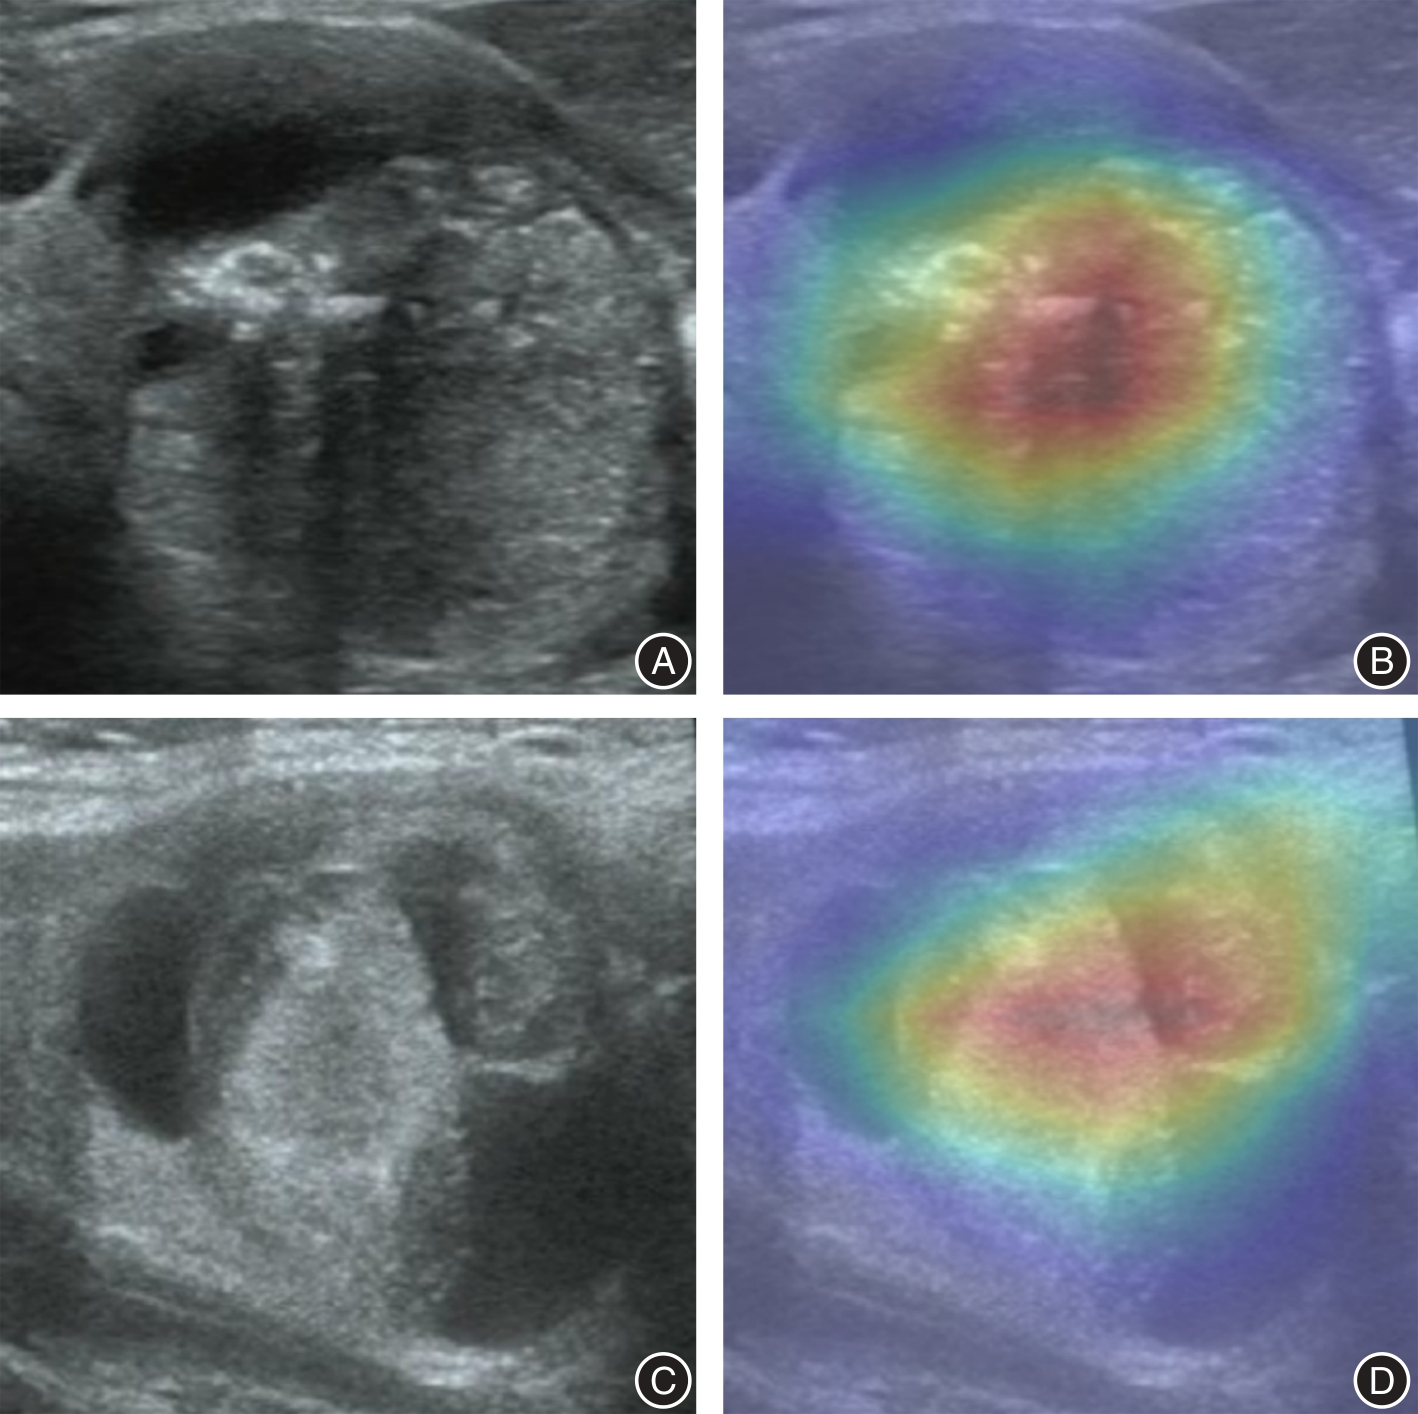

目的 探讨基于超声的迁移学习人工智能模型预测甲状腺囊实性结节(PCTN)恶性概率的可能性。 方法 回顾性分析2021年1月至2023年12月间就诊于山东大学齐鲁医学院威海市立医院并有明确病理结果的PCTN患者246例,以7:3的比例随机分为训练组和测试组。评估PCTN超声图像特征,经过多因素logistic回归分析,得到评估PCTN恶性概率的独立危险因素并计算曲线下面积(AUC)。另一方面,通过Python软件的PyTorch框架对数据进行预处理后,选择5种不同的预训练模型进行迁移学习,具体包括Inception_v3、EfficientNet、VGG19、ResNet50和DenseNet121,计算AUC值并进行比较。 结果 超声图像特征中实性成分> 50%、实性成分与囊性成分呈偏心锐角、病灶边界模糊不清、病灶边界呈毛刺样、蛋壳样钙化和微钙化对于评价PCTN的良恶性差异有统计学意义(P < 0.05),基于以上独立危险因素计算的AUC值为0.843。另外,在5种迁移学习模型中,ResNet50模型诊断效能最高,AUC值为0.903 2。 结论 基于超声的迁移学习人工智能模型优于传统超声图像评价效能,能够准确预测PCTN的性质,从而减少不必要的超声引导下细针穿刺活检。